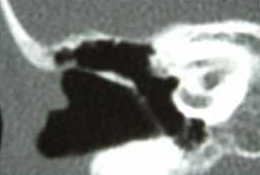

真珠腫性中耳炎は聴力低下、めまい、顔面神経麻痺や頭蓋内合併症を生じる可能性のある疾患である。このため真珠腫性中耳炎の手術においては真珠腫上皮の完全除去が第一の目標となる。手術において真珠腫上皮が残存するといわゆる遺残性再発となり、再び種々の合併症の危険性が生じる。また、炎症の強い中耳腔に伝音連鎖の再建を行った場合には中耳腔内の換気ルートが阻害され、再形成性真珠腫を生じやすくなる。このため、多くの施設では真珠腫性中耳炎に対しては段階手術が行われている。初回手術で真珠腫の摘出を行い、6ヶ月から1年後に計画的に第2回手術を行い、中耳腔の安定化した状態で遺残真珠腫の確認、摘出と伝音連鎖再建による聴力改善を図る。図のように初回手術前にはまったく含気の認められない中耳腔が第2回手術前に正常化することが理想であり、このような状態となれば聴力改善も容易となる。

図 手術による中耳含気腔の形成